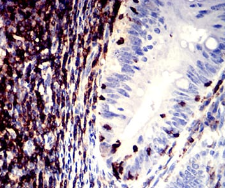

IHC    1/200 - 1/1000